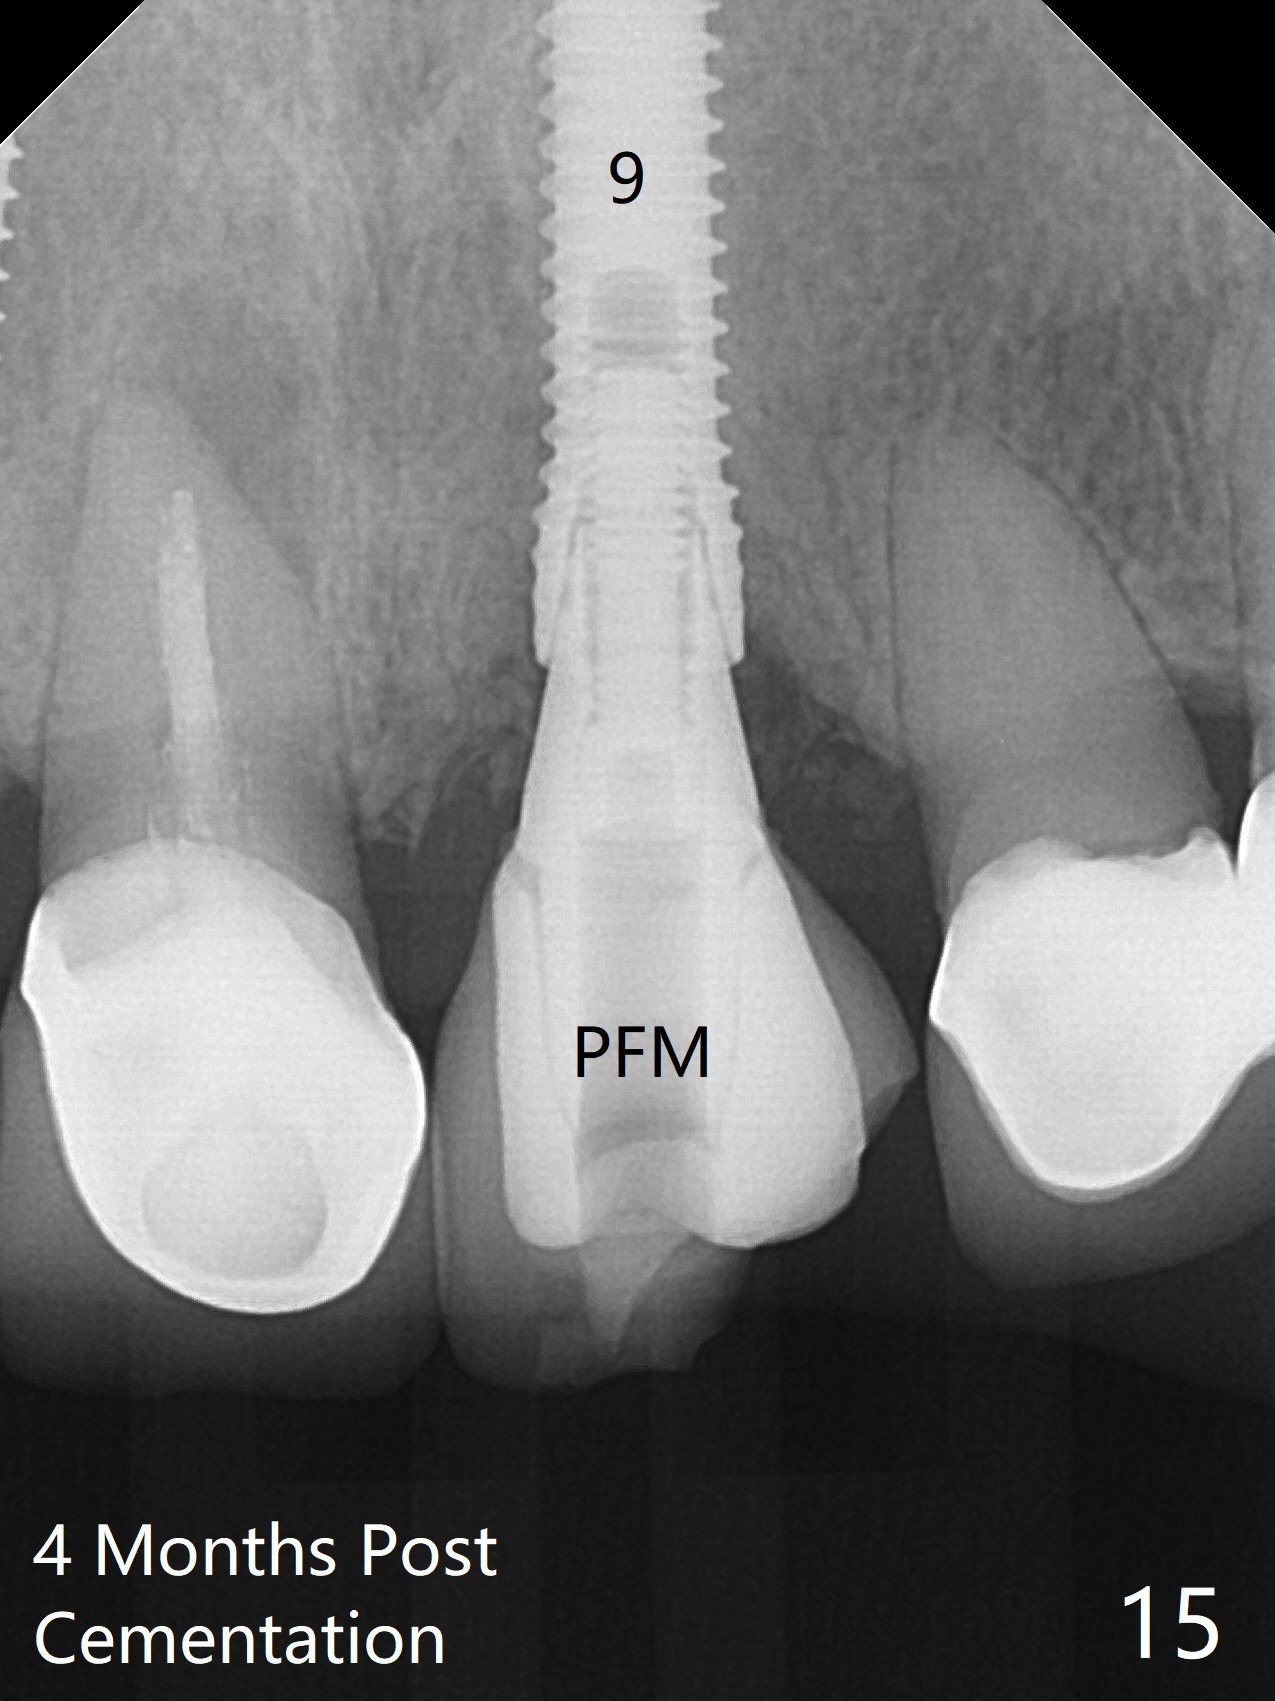

The buccal contour at #9 seems to be slightly concave preop (Fig.1,2 (*)). In fact the buccal plate is found to be lost when the tooth is extracted. Osteotomy is initiated as palatal as possible apical, but the occlusion dictates the coronal end of the osteotomy should be buccal, leaving the buccal gap ~ 2 mm for bone graft. The initial osteotomy (18 mm deep) appears to be close to the Incisive Foramen (Fig.3 blue dashed line). The nasal floor appears to be intact when the drill is removed. Subsequent osteotomy is adjusted so that the apical end of the osteotomy moves distal; when a 3.8x15 mm dummy implant is partially placed, there is clearance (Fig.4). It remains so when a definitive implant is seated (Fig.5); Vanilla graft is placed (Fig.5 *) before placement of a 4.5x5.5(3) mm abutment. More allograft is placed when an immediate provisional is fabricated (Fig.6 arrow and *). The gingiva remains to be recessive 1 month postop (Fig.7). It seems to be related to the bulky gingival margin of the provisional (Fig.8 *). After trimming the latter (Fig.9 *), the gingival margin immediately returns close to normal (Fig.10). The gingival margin is even between #8 and 9 two months postop, but the bone graft is exposed apically (Fig.11 ^). It may heals by itself. Otherwise debridement, regraft, PRF and suture are pending. The coronal portion of the socket heals 4 months postop (Fig.12). The gingival cuff forms by the immediate provisional (which is removed for impression) 4 months postop (Fig.13 *). While the full Zirconia crown at #7 remains intact (Fig.14), the PFM at #9 has porcelain chip (Fig.15). It is partially due to the occlusion; while the crown at #7 has clearance with the opposing dentition (Fig.16 *), the one at #9 has no. The access hole at #9 (Fig.17 *) seems to weaken the crown structure. There is no access hole at #7. No solid posterior support is another contributing factor for chip (Fig.18). The buccal plate has mild atrophy at #7 and 9 (Fig.19 *). A piece of bone graft is being expelled apically at #9 (Fig.20 >) and is removed subsequently (Fig.21). Before impression for repacking porcelain, the opposing incisal edge has been shortened (Fig.22 arrows, as compared to Fig.16). Since the ideal access hole is at the incisal edge (Fig.25 black circle), buccal to the existing one (Fig.24 A), the abutment is torqued before the repaired crown is recemented (Fig.23). Finally the crown has occlusal clearance (Fig.26). Porcelain chips again around the access hole of PFM 1.5 years post 2nd cementation. The dense bone at the crest (*) cannot explain why the abutment is not loose, since it remains incompletely seated (>). As it was trimmed short, an angled abutment is used (Fig.28). The coronal end is lingual, while #9/24 is edge to edge. The lingual aspect of the coronal end of the abutment is heavily trimmed to reduce bulkiness. To prevent chip, Zirconium crown will be fabricated in spite of the fact that it does not match the PFM of #8 (potential shade discrepancy). The patient is pleased with the new Zirconia crown (Fig.29).